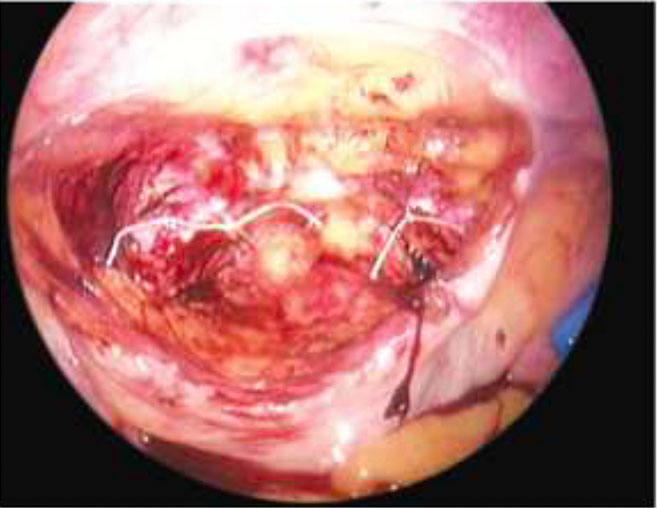

In the correct plane, the bladder can be pushed below the cervix without needing extensive separation from the vagina, thereby reducing the risk of bleeding. In the event of a bladder injury, a two-layer closure (Figure 8) is recommended, after which the primary surgery can be continued.

(a) |

(b) |

8

Bladder injury before (a) and during (b) suturing, using a two-layer closure technique.

Bladder injury

During dissection or energy-source injury, the size and location of the bladder injury (Figure 8A), as well as its proximity to the ureteric orifices, should be identified. The bladder should be mobilized to allow repair with healthy tissue margins, followed by a two-layer closure; the choice of suture may vary (Figure 8B). In some cases, placement of a ureteric DJ stent may be necessary. The planned surgical procedure should then be continued. The Foley catheter should typically be left in place for 7–14 days, depending primarily on the nature and extent of the energy-source injury.